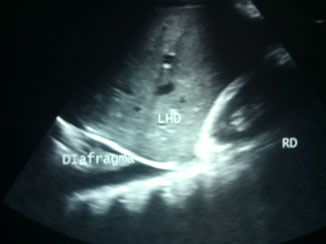

Hombre de 42 años, de complexión delgada y sin antecedentes médicos de importancia. Presentó cuadro de dolor abdominal, de aparición súbita y de moderada intensidad en epigastrio con dos semanas de evolución. El dolor era opresivo con irradiación a hipocondrio derecho, además de náuseas y malestar general; acudió al servicio de Urgencias ante la sospecha de colecistitis crónica litiásica agudizada. Se le hizo ultrasonografía (USG) abdominal (figura 1), la cual reportó hepatoesplenomegalia con lodo biliar vesicular y derrame pleural derecho.